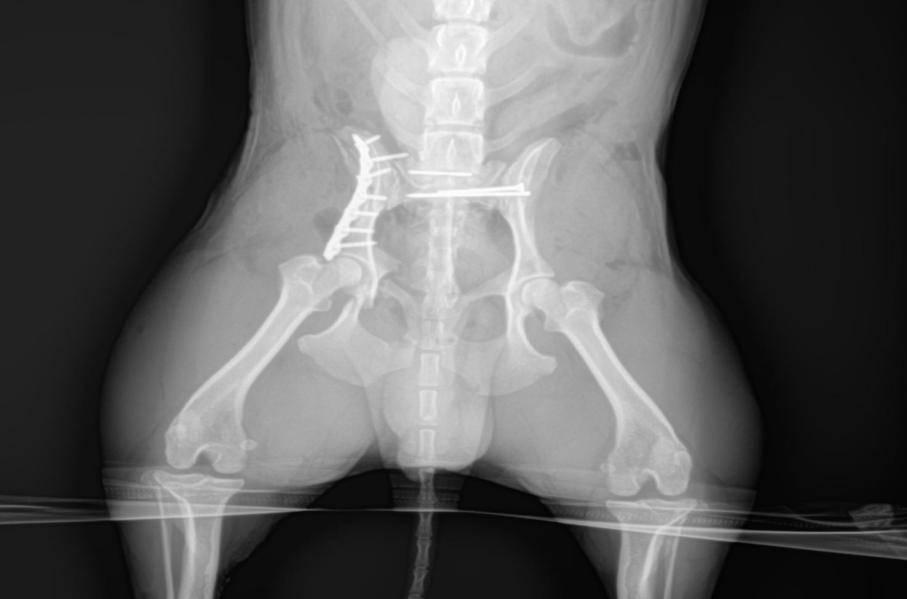

3.4 髂骨体骨折内固定:将犬以同上方法左侧卧保定,皮肤切口始于髂嵴中心,向后延伸至大转子后下缘。切开皮下组织、臀部脂肪和浅筋膜,并与皮肤一同牵引开。沿皮肤切口线,切开臀深筋膜,以便切开阔筋膜张肌与臀中肌之间的肌间隔。该切口从髂腹侧棘向后延伸至股二头肌前缘。也可沿股二头肌前缘切开筋膜,形成一个T形筋膜切口。牵开臀中肌,显露臀深肌和部分髂骨体。在骨中肌起点作一切口,始于髂腹侧棘后侧,根据需要可向前背侧延伸。臀中肌和缝匠肌的肌纤维交织在一起,需在两肌间作部分锐性分离。结扎位于髂骨腹侧缘的髂腰血管。开始切开臀深肌起点,以便将该肌向后牵引。 骨膜下剥离诸臀肌,显露髂嵴、髂骨翼和髂骨体。髂骨体和髋臼前缘显露过大有可能损伤分布到阔筋膜张肌的臀前动、静脉和神经的分支。沿髂骨体腹侧缘分离髂肌,常导致切断髂骨体腹侧面的一营养动脉。被切断的动脉必须烧烙或用骨蜡堵塞止血。复位钳复位骨折部位,骨板塑性后采用临时固定螺钉在两侧进行临时固定,采用1.5mm钻头在断端钻孔采用2.0皮质自攻螺钉固定,其他螺钉分别按顺序植入,3/0Monosyn将臀中肌筋膜和缝匠肌缝在一起,沿此缝合线连续向后缝合臀中肌和阔肌膜张肌,分层缝合臀深脂肪和筋膜.皮下组织和皮肤。